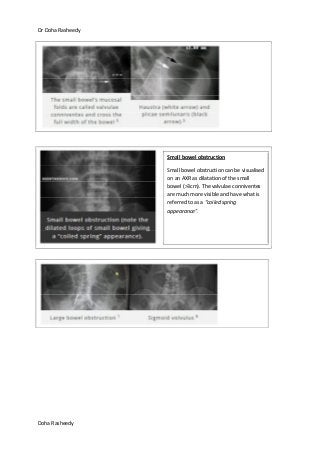

Small bowel obstruction – features

>3cm, multiple air fluid levels>2, some in the same loop at differe thights

>3cm, multiple air fluid levels>2, some in the same loop at different hights

Features of small bowel obstruction include the central position of gas-filled and distended loops of

bowel.

The white lines passing across the full width of the bowel are 'valvulae conniventes' - these are only

found in the small bowel.

Small bowel obstruction

Small bowel obstruction can be visualised

on an AXR as dilatation of the small

bowel (>3cm). The valvulae conniventes

are much more visible and have what is

referred to as a “coiled spring

appearance”.